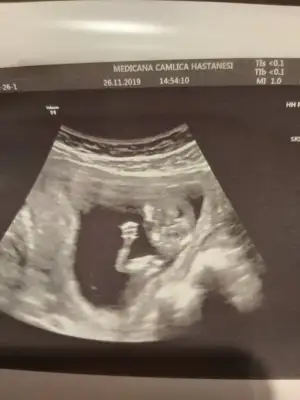

Bana da de banada attım resminiaaa nuba göre erkek canm kaç haftalıktı bu usg

Erkek mi ki acabaTeyzeler bu da bizim fotomuz ☺